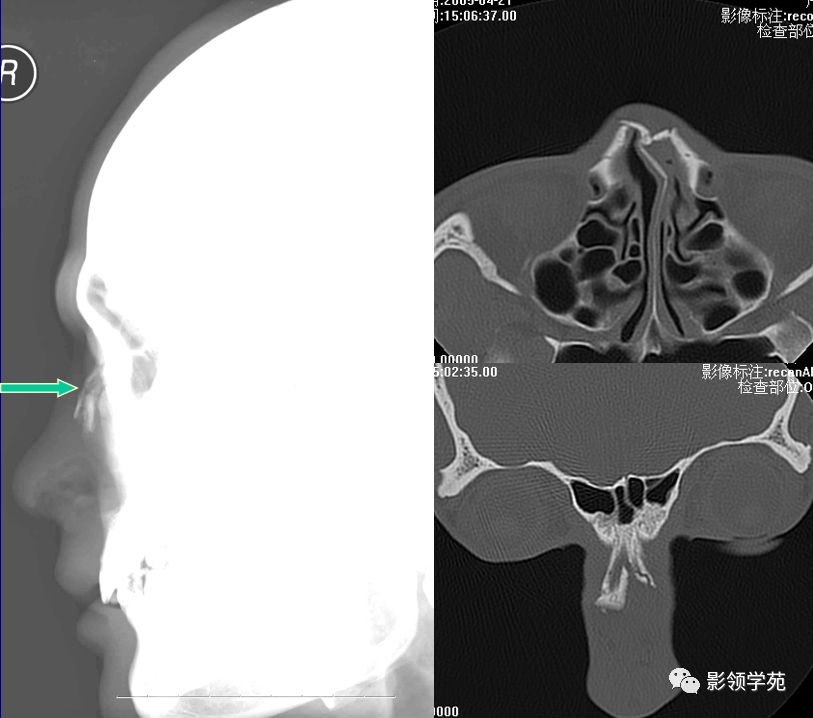

X线平片:侧位

HRCT

- 横断面:听眶下线

- 冠状面:鼻骨长轴平行线

- 层厚:1~2mm

右侧鼻骨线形骨折

鼻骨线形骨折

左侧鼻骨线形骨折

右侧鼻骨骨折

左上颌骨额突骨折